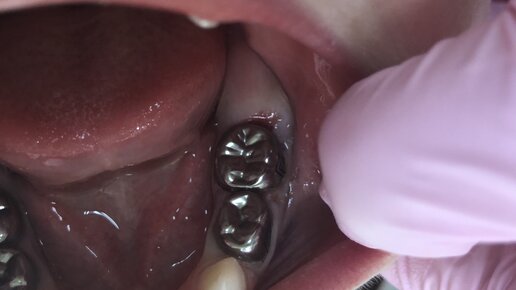

Зачем восстанавливать зуб коронкой у детей